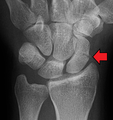

A more obvious scaphoid fracture on a scaphoid view X ray